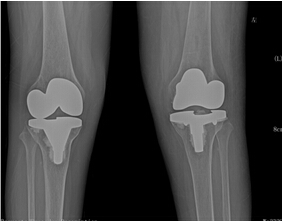

來院后,骨科二區(qū)唐雄主任、廖浩主治醫(yī)師熱情接待了她。經(jīng)查,患者為嚴(yán)重的類風(fēng)濕性關(guān)節(jié)炎導(dǎo)致的雙膝關(guān)節(jié)破壞,雙膝關(guān)節(jié)內(nèi)翻畸形并嚴(yán)重的骨質(zhì)缺損,同時由于患者長期服用激素類藥物,其全身骨質(zhì)均有嚴(yán)重的骨質(zhì)疏松。患者得知病情嚴(yán)重性后,感到失望、沮喪,唐雄主任信心滿滿地安慰道,“您這種情況行膝關(guān)節(jié)置換術(shù),就能徹底解決關(guān)節(jié)疼痛和雙膝關(guān)節(jié)不能活動的問題?!庇谑?,病人又重新燃起了對生活的希望,并要求盡快進(jìn)行手術(shù)治療。

考慮到患者為長期慢性病病人,唐雄主任決定先給患者疼痛程度更高的右側(cè)膝關(guān)節(jié)進(jìn)行手術(shù)治療。經(jīng)過完善備血、調(diào)整激素用量等術(shù)前準(zhǔn)備后,2015年10月10日,唐主任為患者進(jìn)行了右側(cè)膝關(guān)節(jié)人工關(guān)節(jié)置換術(shù),術(shù)后患者恢復(fù)良好。右側(cè)膝關(guān)節(jié)疼痛解除,術(shù)后3天右下肢能下地活動。出院后,患者對右側(cè)膝關(guān)節(jié)置換術(shù)的效果非常滿意。 2016年7月17日,唐主任為該患者再次進(jìn)行了左膝關(guān)節(jié)人工關(guān)節(jié)置換術(shù)?;颊咝g(shù)后3天就能下地活動?,F(xiàn)在她的臉上又出現(xiàn)了燦爛的笑容,她逢人就說,要是早一點來手術(shù)治療,就能早一點擺脫病痛的折磨了。